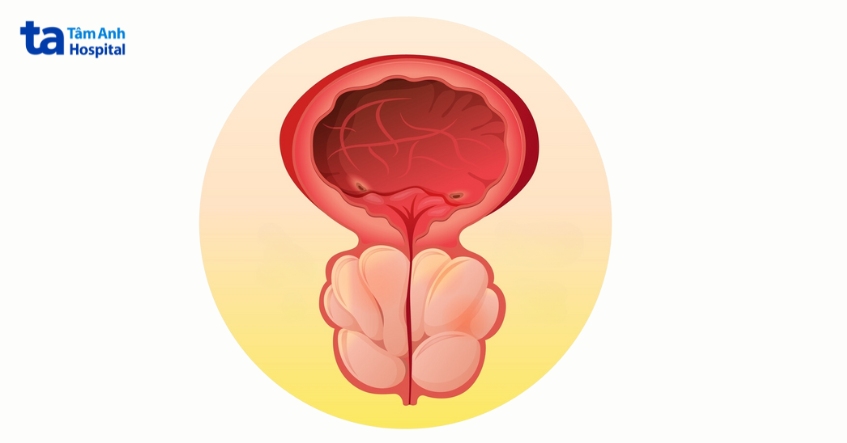

Tuyến tiền liệt là tuyến có kích thước bằng quả óc chó chỉ có ở nam giới, nằm giữa dương vật và bàng quang, quấn quanh niệu đạo (ống dẫn nước tiểu ra khỏi cơ thể). Viêm tuyến tiền liệt gây đau và sưng tuyến tiền liệt, khiến việc đi tiểu trở nên khó khăn và khó chịu. Có 4 loại viêm tuyến tiền liệt chính: